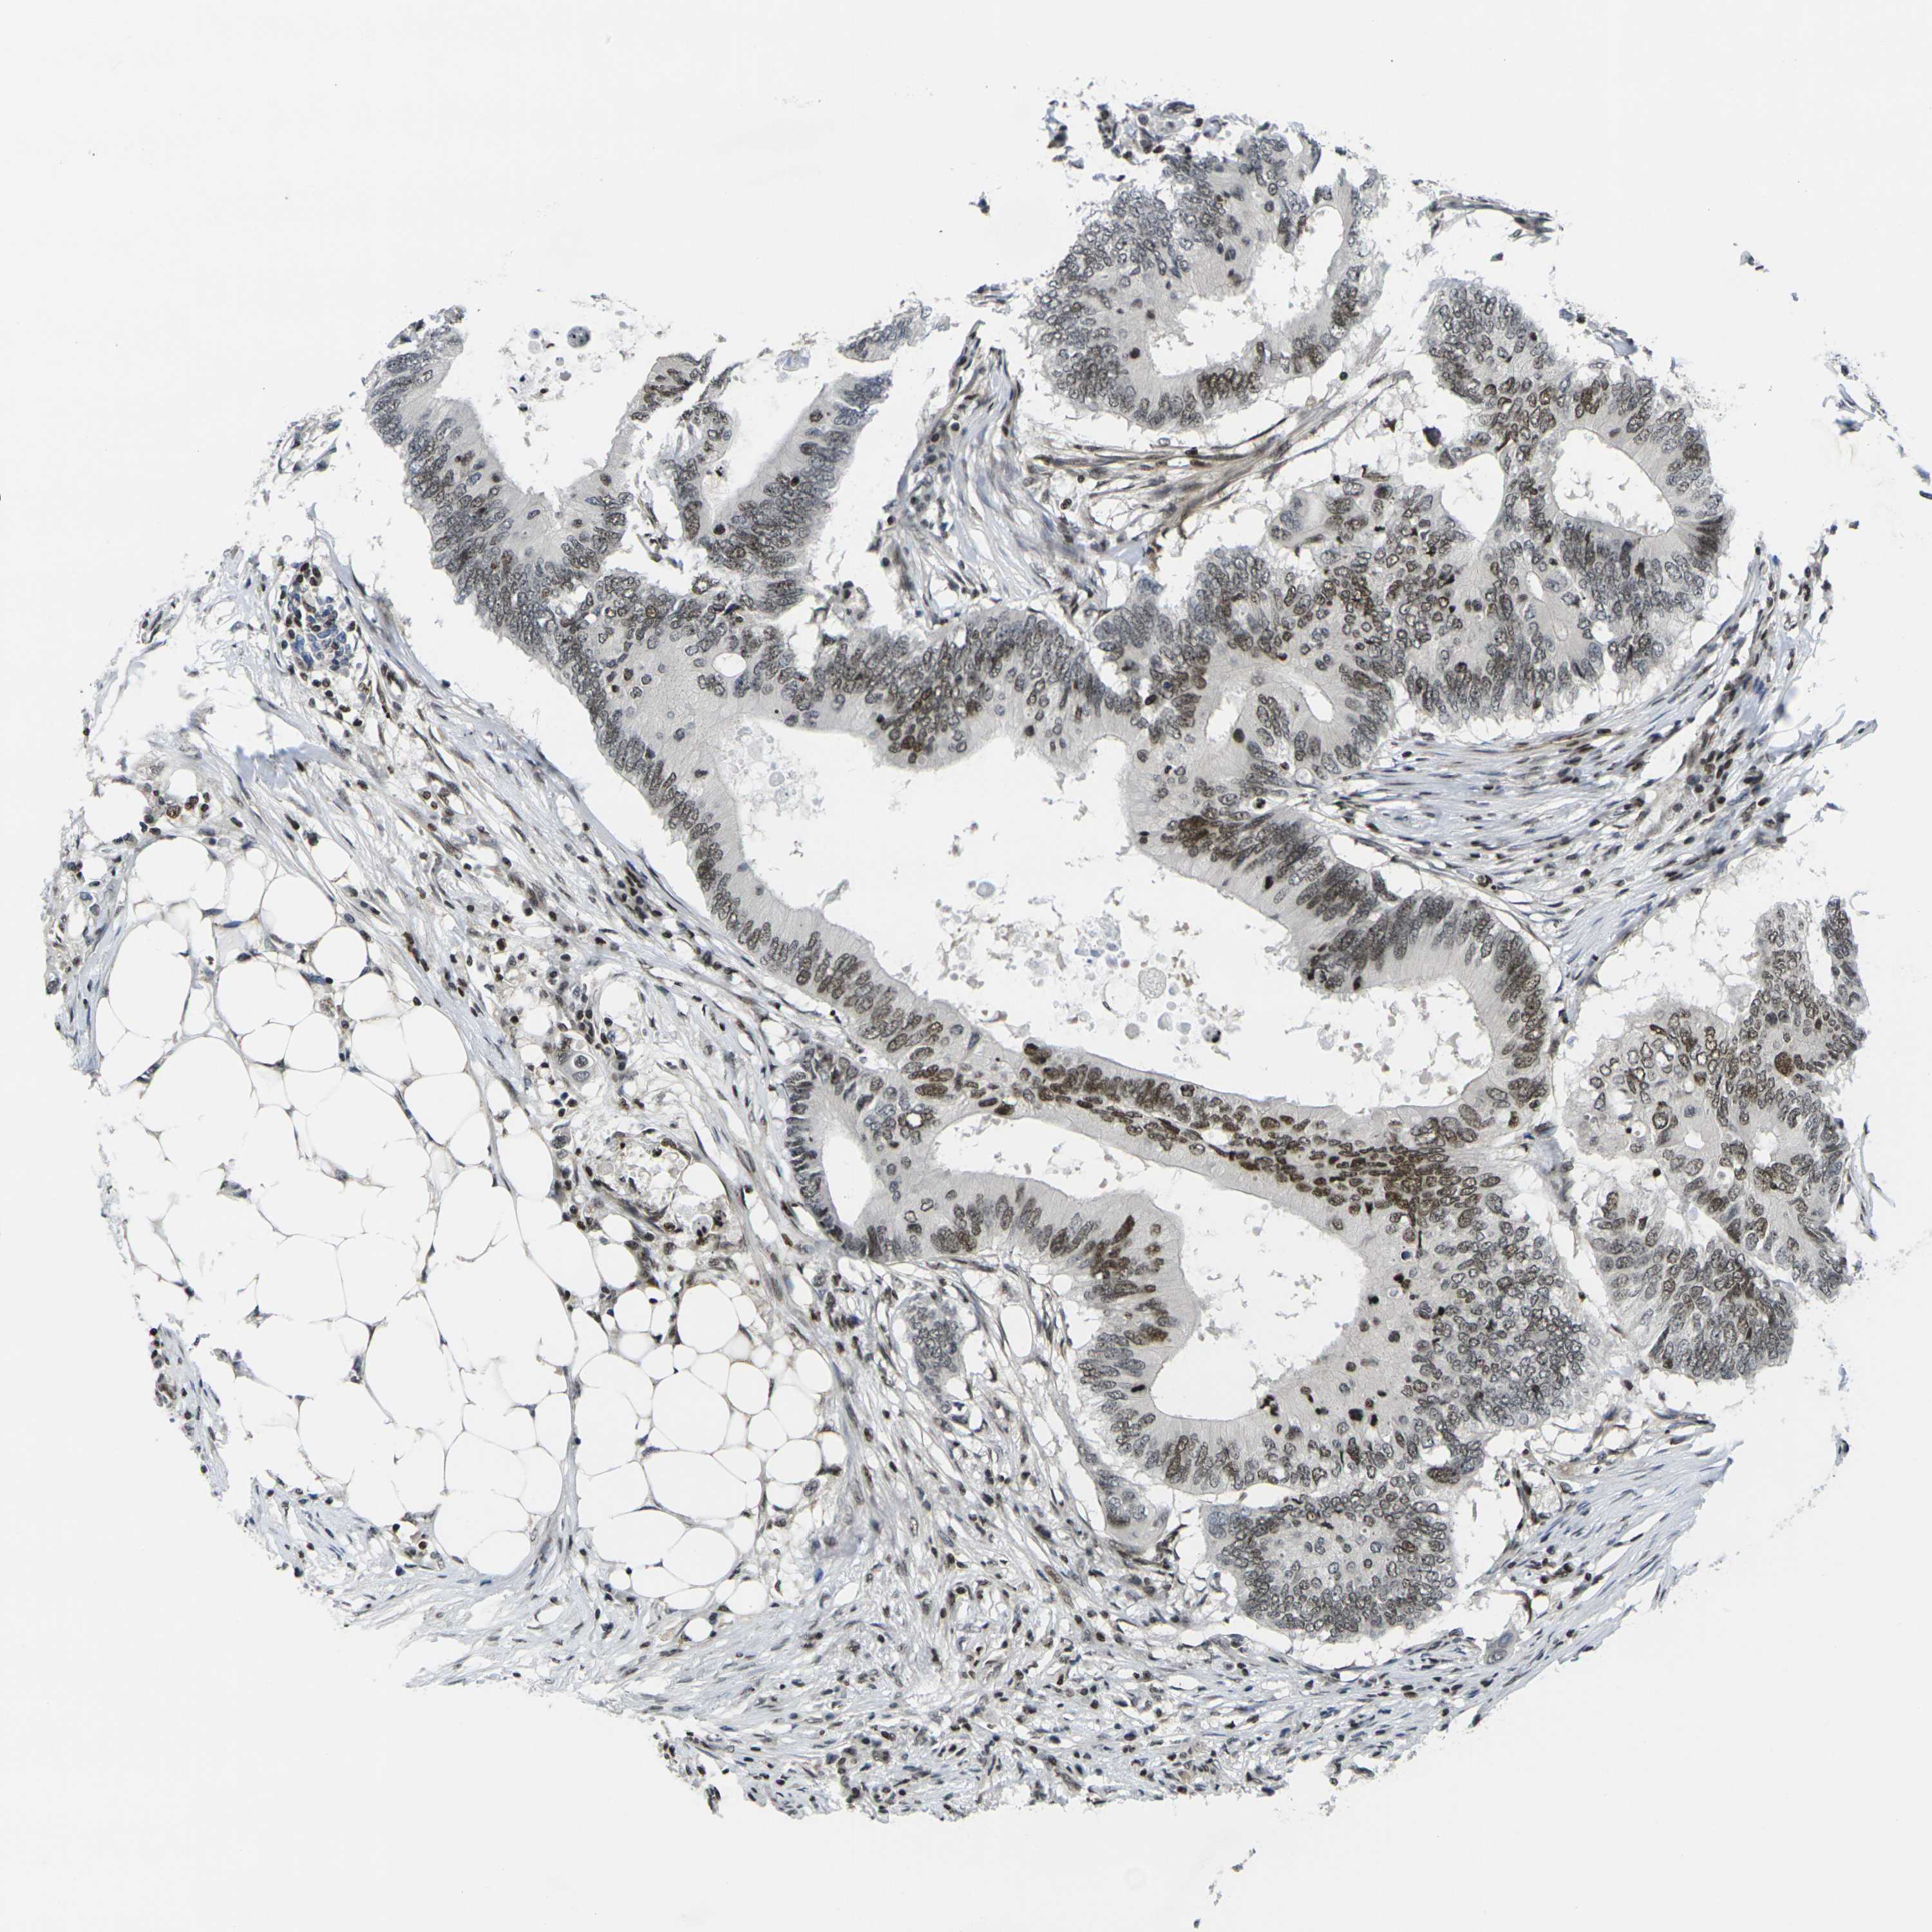

CANCER COLORECTAL CANCER Show tissue menu

Colorectal cancer

Human cancer

Colon adenocarcinoma